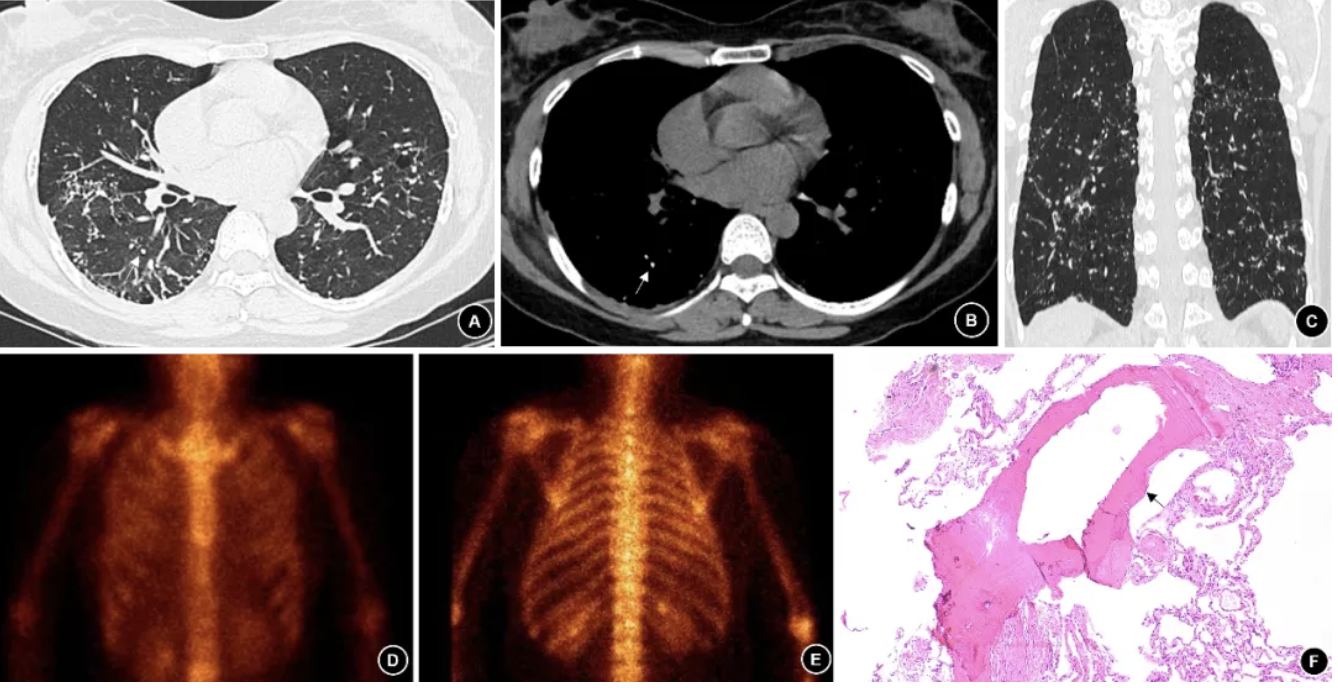

图2. (例2患者)2023年8月胸部CT,肺窗(A)、纵隔窗(B)、冠状面(C)见双肺弥漫性分布高密度小结节及细线状影,小叶间隔增厚,斑片状的磨玻璃影,纵隔窗可见点状钙化影,分布较密集(白色箭头);2024年7月骨显像,前位局部(D)、后位局部(E)示双侧中肺放射性摄取弥漫稍增高;(F)TBCB右下肺组织内可见一处成熟骨组织(黑色箭头),其中可见脂肪空泡(HE染色 ×200)。

4. 胸部影像学及肺功能表现:4例的胸部CT(图1-4 A-C)主要表现为双肺弥漫性高密度小结节伴钙化、散在分支样细线状影、胸膜轻度增厚。其中2例患者完善99mTc-亚甲基二膦酸盐(Methylene diphosphonate, MDP )全身骨显像(ECT)发现双肺放射性摄取弥漫增高,考虑骨外摄取(图2-3 D-E)。肺功能测试显示3例轻度阻塞性通气功能障碍, 1例限制性通气功能障碍,3例伴弥散功能轻度下降(表2)。

5. 病理学表现:4例诊断均经肺活检病理结果证实。1例在胸腔镜下行外科肺活检(Surgical lung biopsy, SLB),术中发现胸膜表面弥漫性分布粟粒样质硬结节,行楔形切口留取样本;2例行经支气管冷冻肺活检(transbronchial cryobiopsy, TBCB),获得3-4块直径约0.5 cm的肺组织标本;1例行经支气管肺活检(Transbronchial lung biopsy, TBLB)。病理主要表现为镜下观察到肺内成熟骨组织(黑色箭头),其中部分可见脂肪组织(蓝色箭头)(图1D、2F,、3F、4D)。